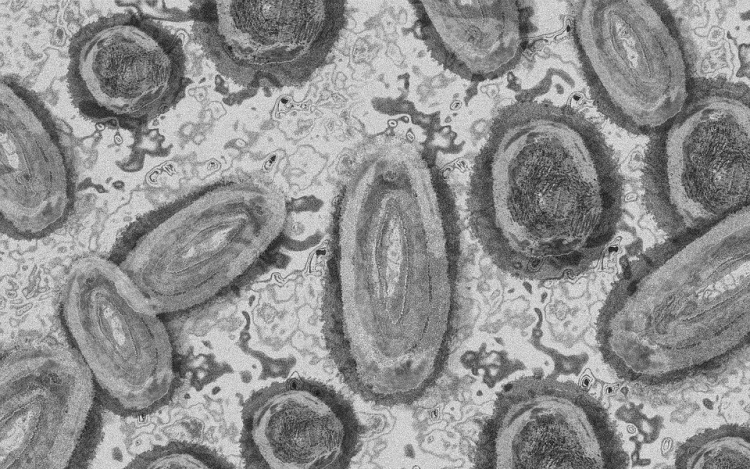

Forrás: mti/illusztráció: pixabay

Belgiumban egy 3 év alatti gyermek fertőződött meg majomhimlővel - számolt be róla szerdán a Sudinfo hírportál.